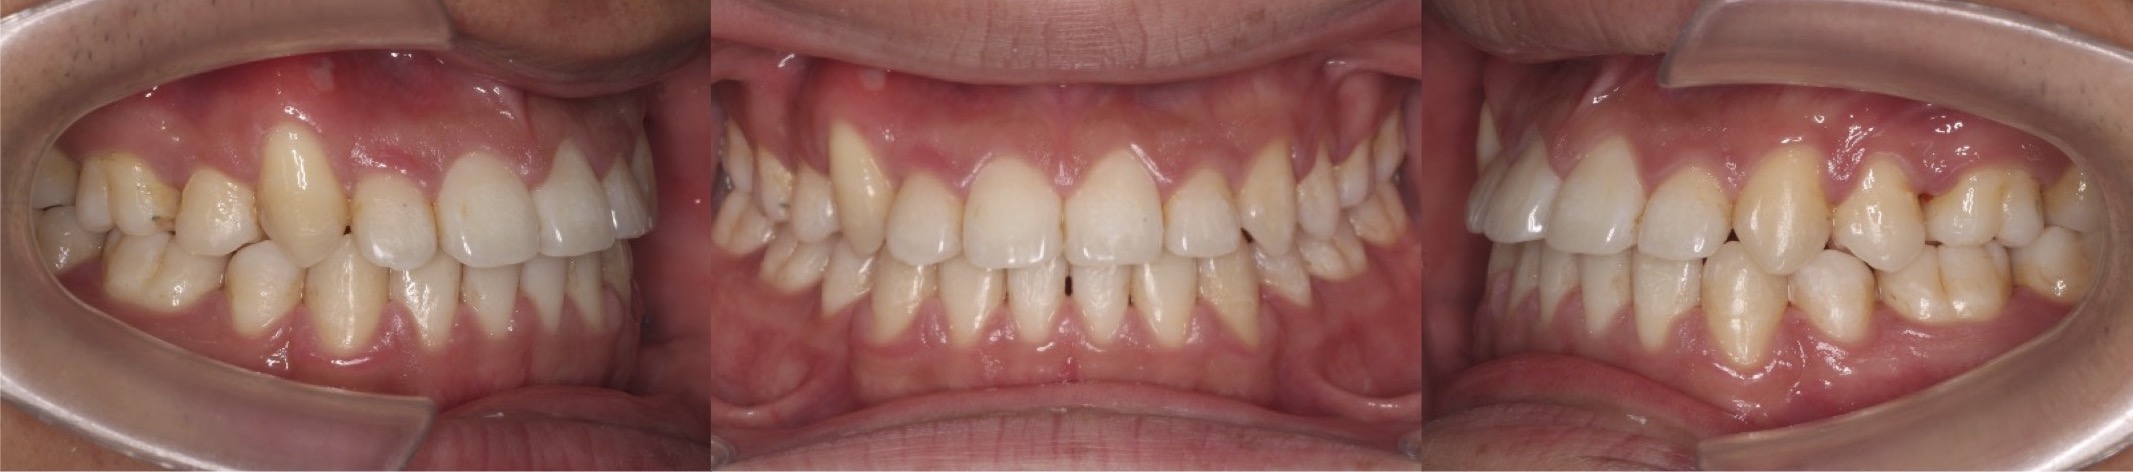

30代男性・マウスピース型装置・非抜歯

<顔のビフォーアフター>

<症例概要>

主訴:受け口

年齢・性別:30代男性

住まい:千葉県八千代市

症状:反対咬合

治療方針:上顎歯列前方拡大・下顎後方移動・IPR

治療装置:マウスピース型矯正装置(アライナー装置)

抜歯:なし

治療期間:1年2か月

アライナー枚数:45+14ステージ

リテーナー:上下クリアタイプ+フィックスタイプ

治療費用:990,000(税込)

代表的副作用:痛み・治療後の後戻り・歯根吸収・歯髄壊死・歯肉退縮

▶︎その他の副作用

【治療シミュレーション】

下の歯並びを奥から順番に後方移動させていきます。III級顎間ゴムをしっかりと使用していただく必要がある治療計画です。

骨格性の要因が少ない、軽度〜中等度の反対咬合です。歯並びのガタガタも少なかったため治療期間は割と短く終わる事ができました。上の前歯が下の前歯乗り越える時は一旦噛みづらい時期がありますが、顎間ゴムをしっかりと使ってくれました。